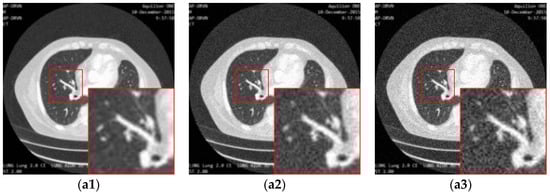

Figure 13 illustrates the performance of different loss functions in restraining the proposed image super-resolution network, including MSE-loss, perceptual-loss, and MSE-perceptual-loss. Using only MSE as a loss function results in the loss of details of the structures in the image, while using the perceptual loss individually leads to blurring and incomplete elimination of noise. In contrast, combining the MSE and perceptual loss can achieve a good balance in the removal of noise and the preservation of structures. The PSNR and SSIM results shown in Table 3 confirm this observation.

Figure 13.

The result of enhancing the quality of images corrupted by noise with different levels and low-resolution through the proposed network with different loss strategies. (a1), (a2) and (a3) are the input images with noise level 5, 10 and 15. (b1), (b2) and (b3) are the ground truth images. (c1), (c2) and (c3) are the images (a1), (a2) and (a3) processed by the proposed network with MSE loss. (d1), (d2) and (d3) are the images (a1), (a2) and (a3) processed by the proposed network with the MSE-perceptual joint loss.

Table 3.

Quantitative results (mean ± std of PSNR and SSIM) associated with different combinations of losses of the proposed network for enhancing the qualities of the images with different noise levels.